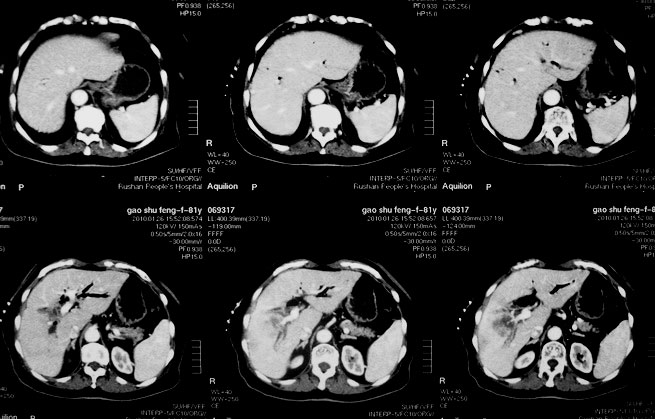

女,80岁既往有胆系手术史。近2月出现食欲不振,近20天出现畏寒发热,体重约下降10kg,体温一般在38℃左右。血常规wbc正常,中性比例88%,cea 10.3,afp、ca199均正常。做过一次肝穿,抽出约3ml仿佛脓性液体。这是她的增强ct扫描,请大家帮帮忙。另外想问问肝脓肿和胆管细胞癌的ct表现有什么区别。谢谢了。

【湘江一滴】化脓性胆囊炎及胆管炎,肝内胆管积气、积液、扩张;胆囊壁增厚、强化;胆周积液。未见肝内占位征象。

【shuiyuan】化脓性胆囊炎及胆管炎,肝内胆管积气、积液、扩张;胆囊壁增厚、强化;胆周积液.

肝脓肿动脉期呈明显环形强化或蜂窝状强化,胆管细胞癌动脉期强化不明显,且伴肝内胆管扩张。

【zenxisengming 】肝内胆管扩张积气,胆囊比环形增厚,胆囊周围渗出,未见占位性病变,应该是胆道化脓性感染

【sunbin】肝内见多个气体密度影伴气液面,胆囊壁增厚,胆囊周围低密度环绕,未见强化,支持化脓性胆管炎、胆囊炎。

最近复查ct,做了第二次穿刺抽脓,顺便做了涂片病理活检,结果找到恶性肿瘤细胞,诊断肝癌合并肝脓肿。看来大家都走眼了啊。